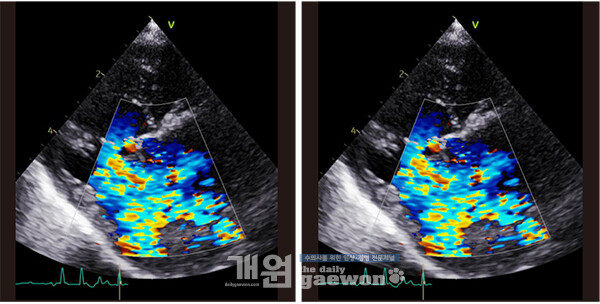

내원 당시 환자는 호흡곤란과 심한 요독증 상태였다. 의료진은 즉시 삽관 후 기계적 환기(인공호흡기 치료)와 지속적 신대체요법(투석·초여과)을 시행해 환자를 안정시켰다. 이후 심장초음파 검사를 통해 정밀 평가를 진행한 뒤 세 차례 투석을 거쳐 체외순환하 이첨판 성형술 및 건삭 재건술을 성공적으로 마쳤다. 수술 후 심초음파 검사에서는 수술 전 심했던 역류가 거의 사라진 것으로 확인됐다.